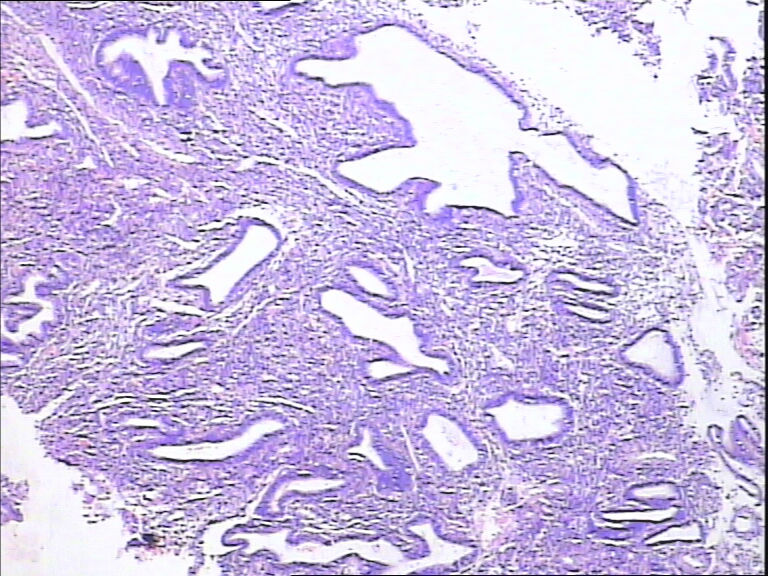

41岁,停经5年再出血。

• 宫内膜图1

图1

腺体增生,部分腺上皮有分泌。

流血期子宫内膜,腺体反应不同步。

片子不是很清楚,像是月经期子宫内膜

是不是采图有问题,片子上细胞变形严重,从轮廓看问题不大,至少不是恶性,再传点图

腺体反应不同步,部分增生期改变,部分上皮细胞有核下空泡呈早分泌期改变,是用过药物?

流血期子宫内膜,腺体反应不同步